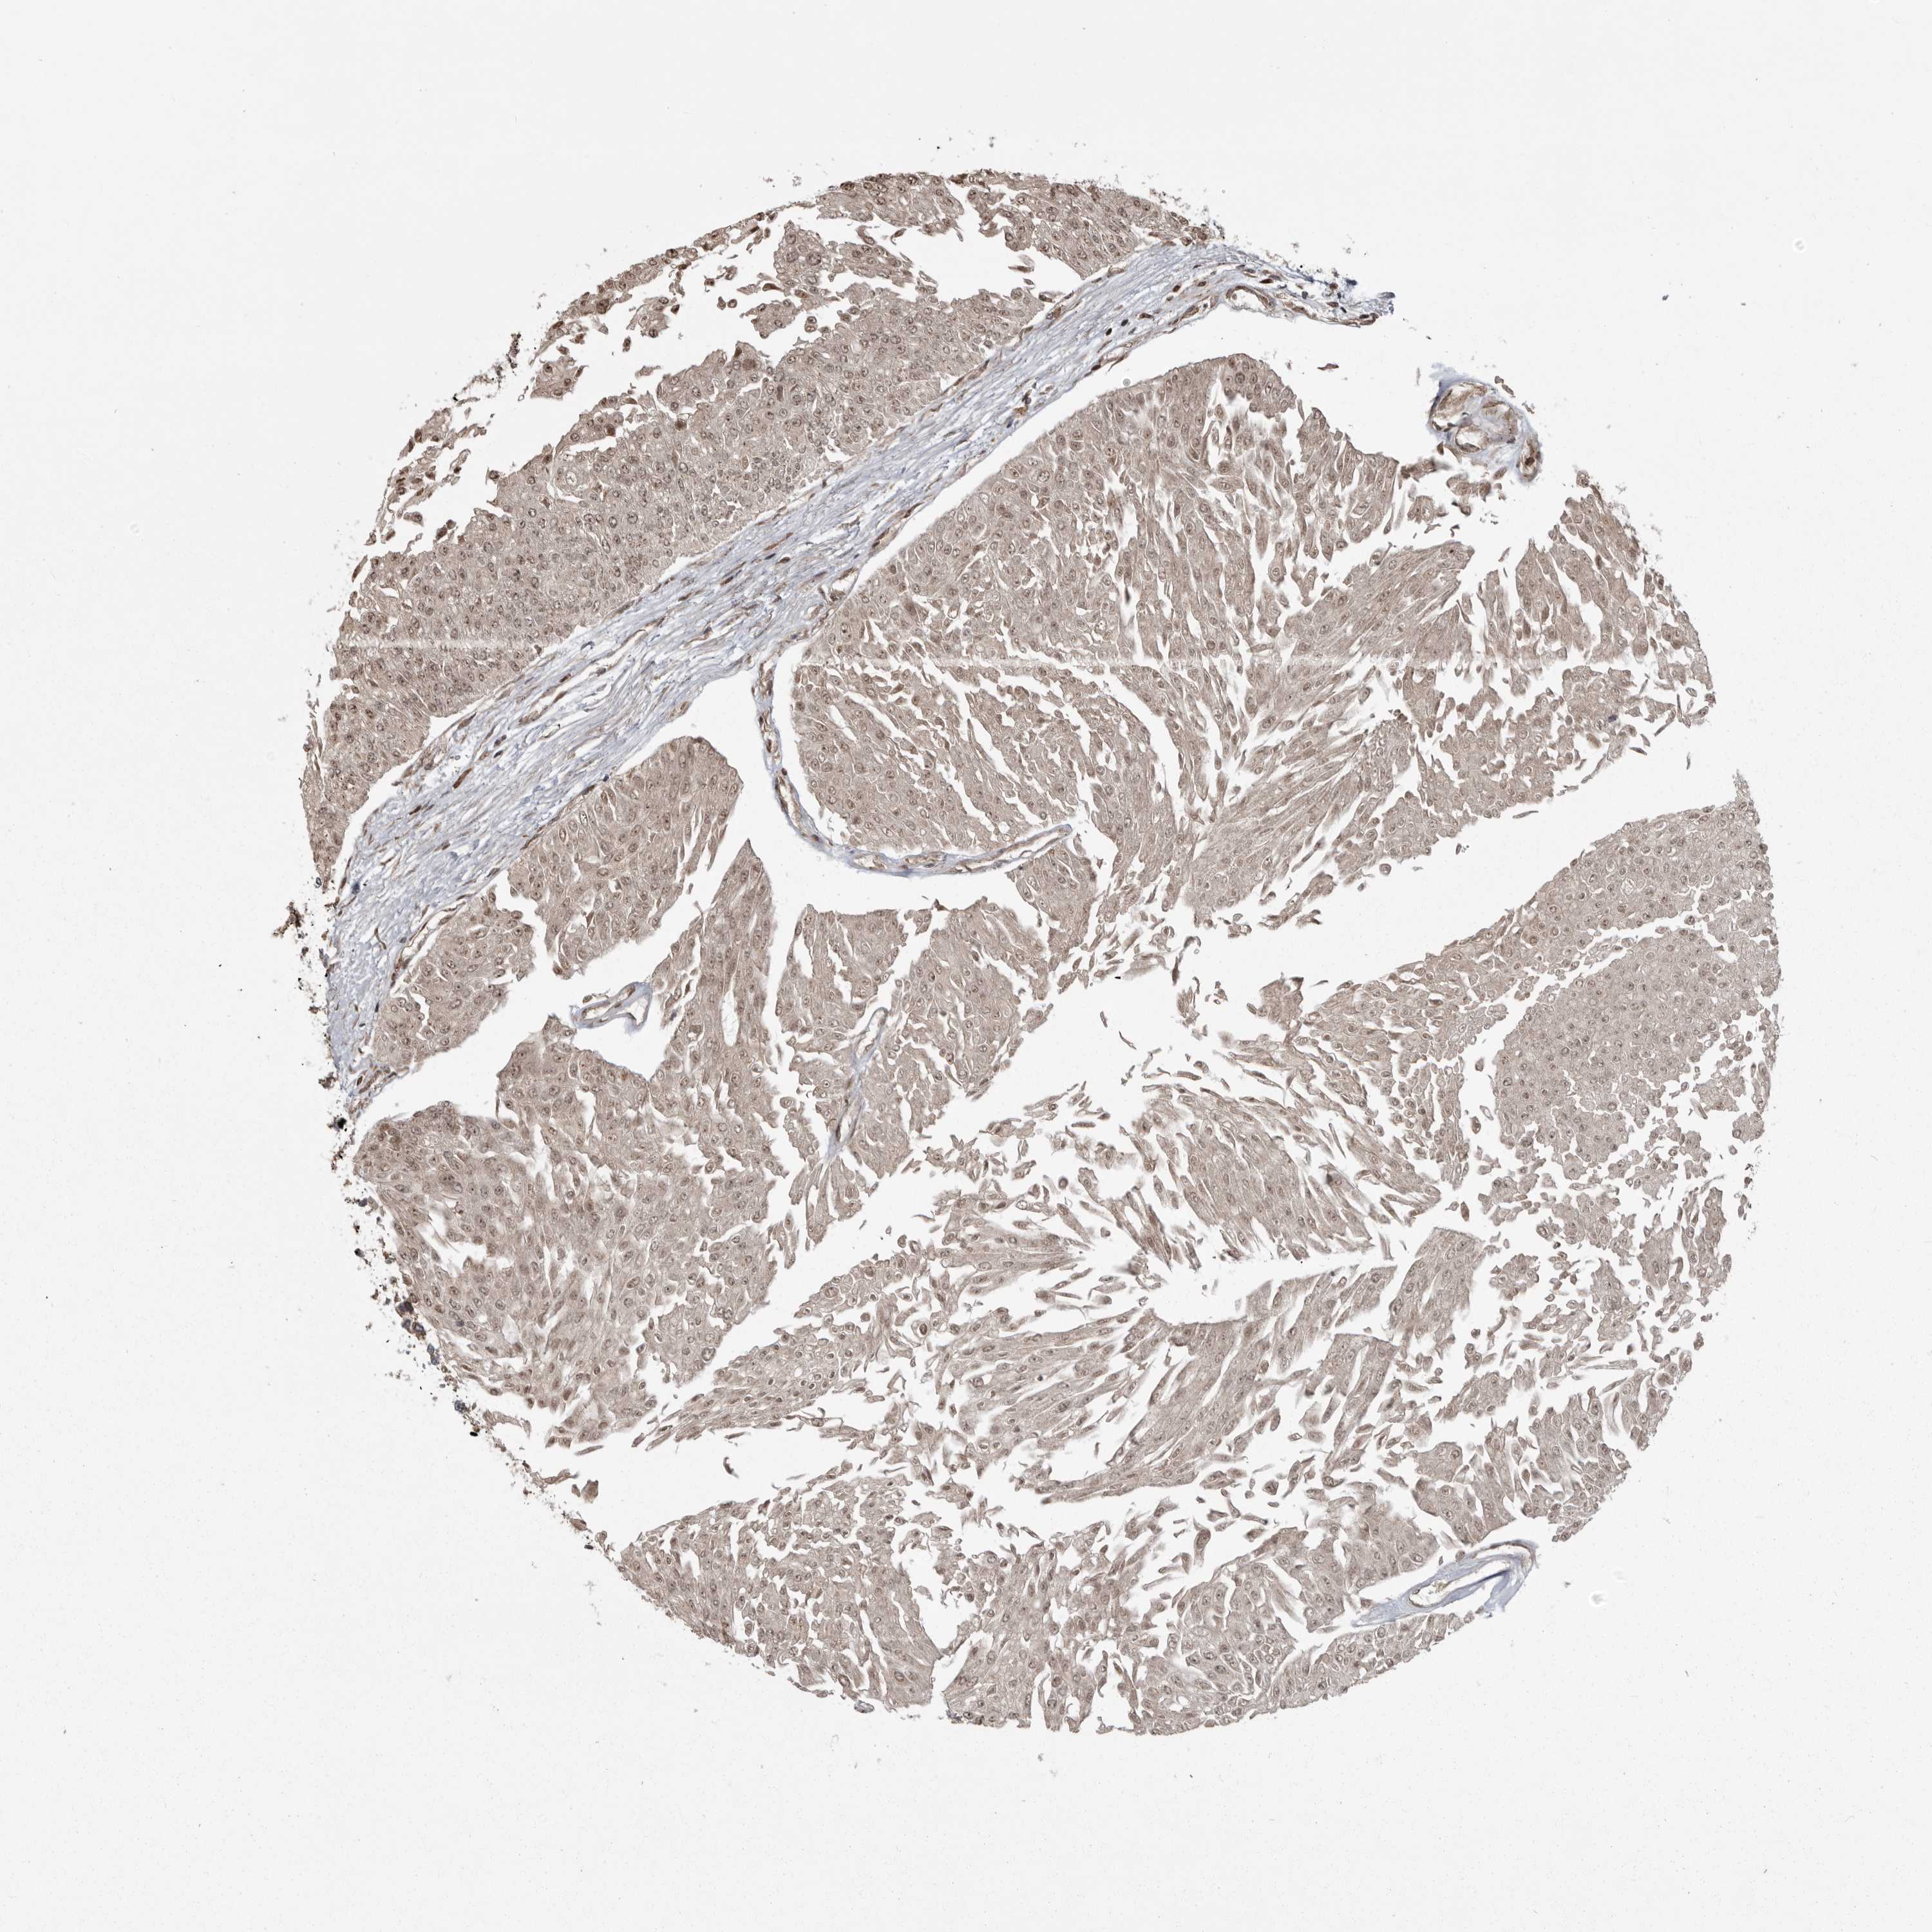

UROTHELIAL CANCER - Protein expressioni

A mouse-over function shows sample information and annotation data. Click on an image to view it in a full screen mode. Samples can be filtered based on level of antibody staining by selecting one or several of the following categories: high, medium, low and not detected. The assay and annotation is described here.

Antibody stainingi

Antibody staining in the annotated cell types in the current human tissue is reported as not detected, low, medium, or high, based on conventional immunohistochemistry profiling in selected tissues. This score is based on the combination of the staining intensity and fraction of stained cells.

Each image is clickable and will lead to virtual microscopy that enables deeper exploration of all samples and also displays staining intensity scores, fraction scores and subcellular localization as well as patient and tissue information for each sample.

Antibody HPA026283

Staining

High

Medium

Low

Not detected

Intensity

Strong

Moderate

Weak

Negative

Quantity

>75%

75%-25%

<25%

None

Location

Nuclear

Cytoplasmic/membranous

Cytoplasmic/membranous,nuclear

Urothelial carcinoma, Low grade

Urothelial carcinoma, High grade